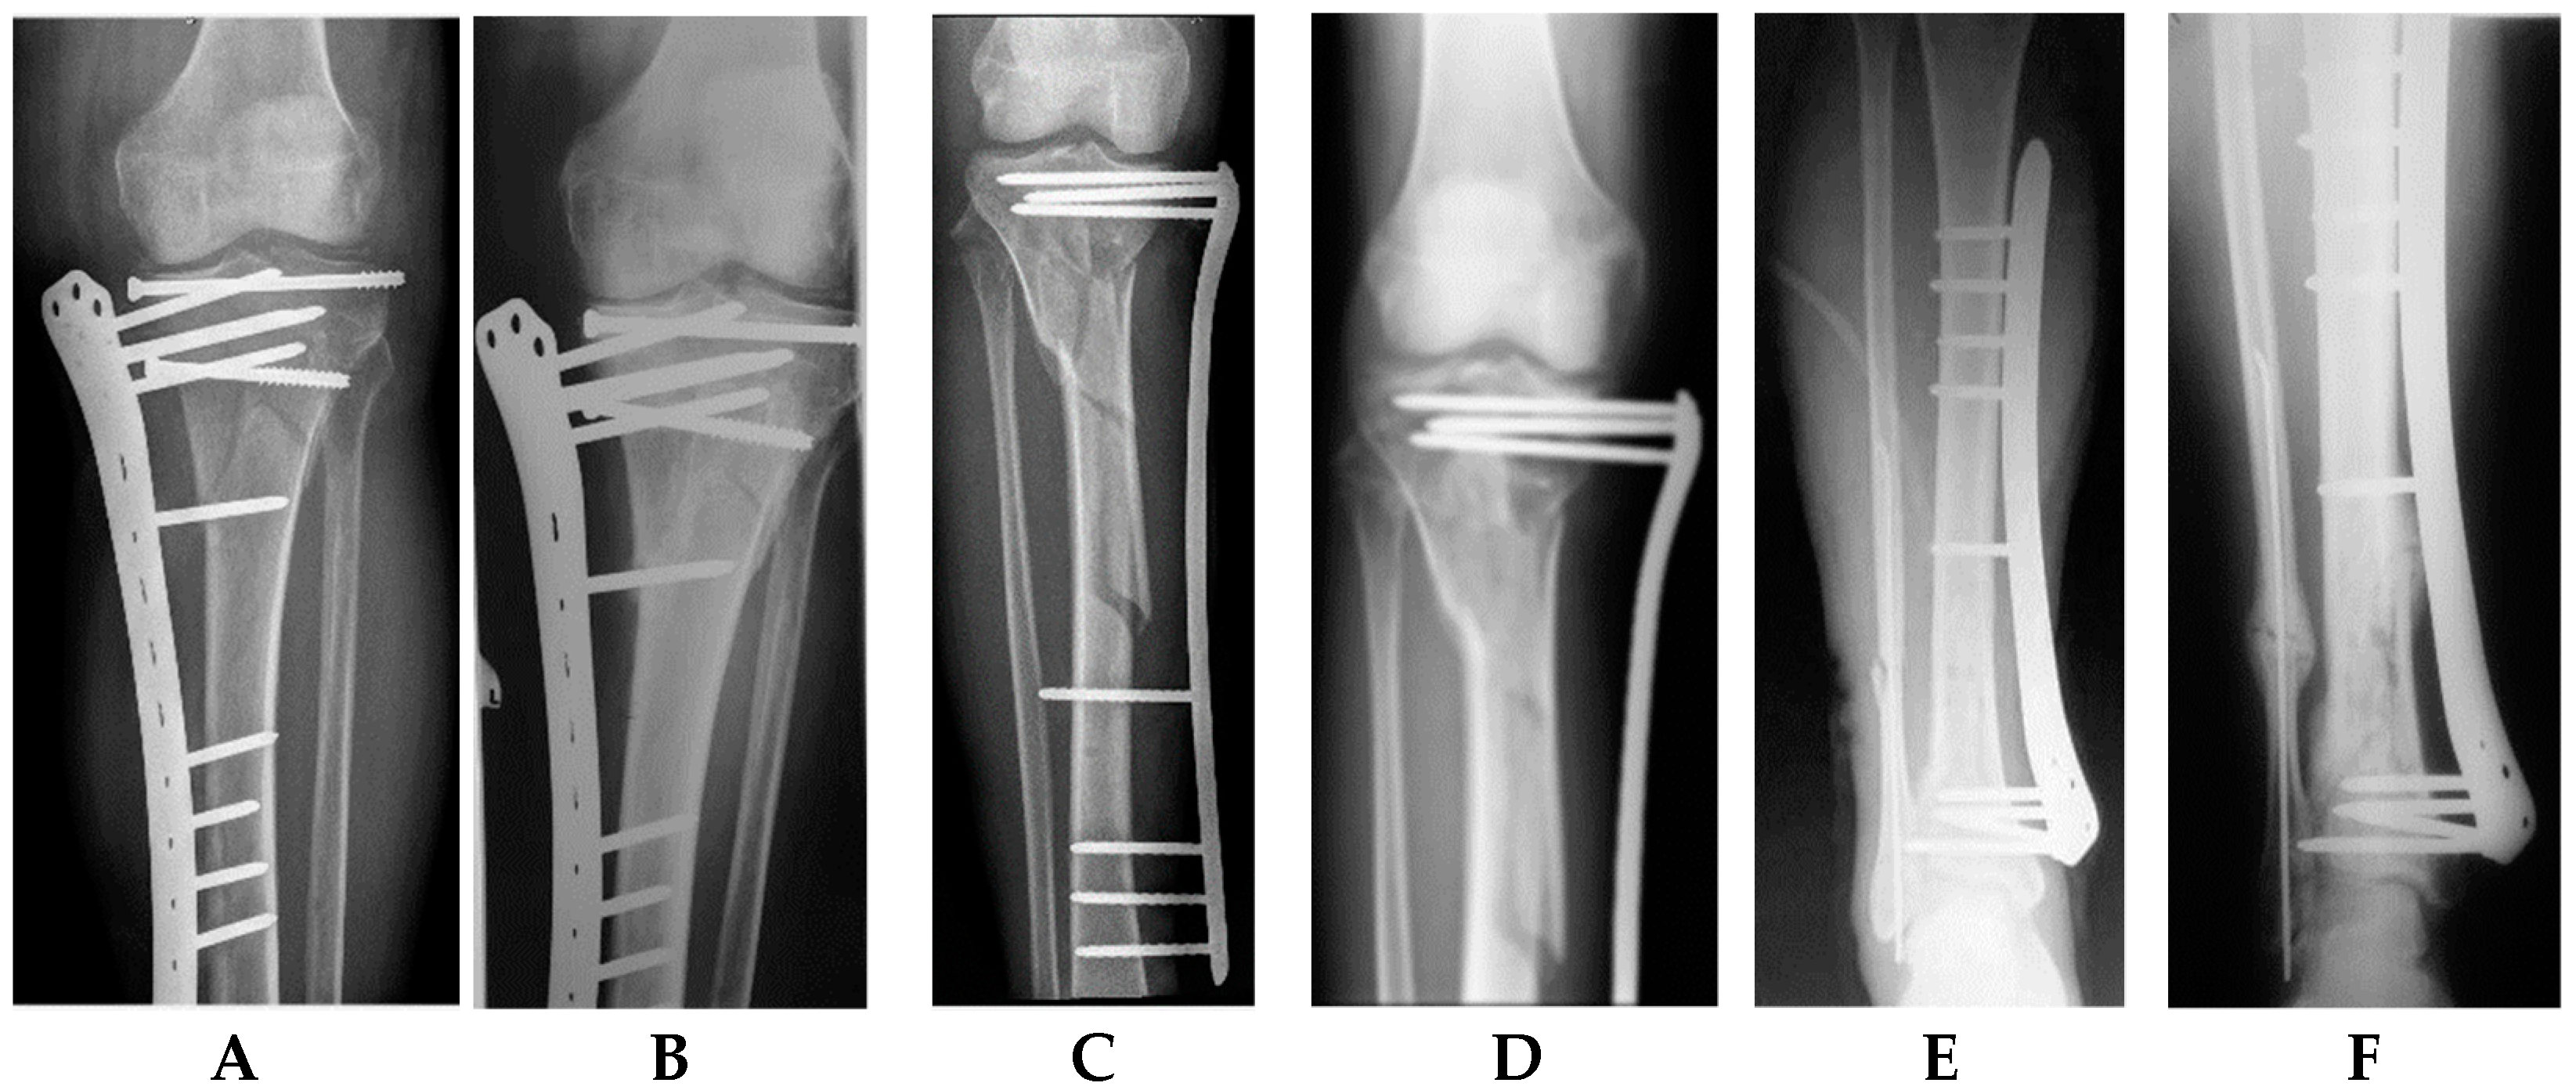

2.2. Surgical Technique

2.2.3. Single-Stage Externalized Locked Plating

2.3. Postoperative Protocol for Active Rehabilitation and Plate Removal